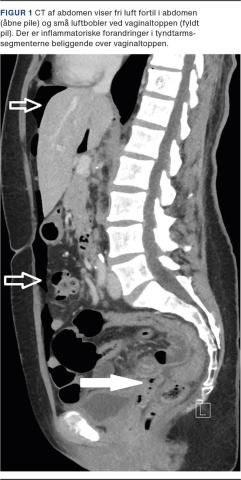

En 59-årig kvinde blev indlagt akut via kirurgisk akutmodtagelse pga. abdominalia. Hun var i 2007 blevet totalt hysterektomeret på benign indikation. Hun var normalvægtig, sund og rask og havde ikke tidligere fået foretaget abdominale indgreb. Hun havde et atypisk smertebillede i form af snigende smerter under højre kurvatur uden udstråling, som i løbet af et døgn flyttede sig ned til nedre abdomen. Hun fremstod ikke akut påvirket, men var lokalt peritoneal suprapubisk. Hun var afebril, havde normalt leukocytniveau og CRP-koncentration på 189 mg/l. Grundet det ikke helt entydige symptombillede overvejede man appendicitis, kolecystitis og ileus som tentative diagnoser. Patienten fik ikke foretaget en gynækologisk undersøgelse. Der blev udført en akut CT af abdomen. CT’en viste fri luft beliggende overvejende op mod forreste bugvæg (Figur 1). Grundet inflammatorisk reaktion omkring tyndtarmssegmenter fik man mistanke om perforeret tyndtarmsdivertikel, hvorfor der blev foretaget eksplorativ laparotomi. Her fandt man komplet ruptur af vaginaltoppen og let peritonitis uden absces lokalt over vaginaltoppen. Den gynækologiske bagvagt blev tilkaldt, og sammen lukkede man vaginaltoppen nedefra i to lag og lukkede abdomen. Ved efterfølgende gennemgang af skanningen så man små luftbobler i vagina og over vaginaltoppen (Figur 1).